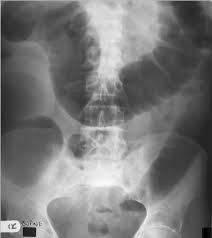

2 from Symptoms of diverticulitis and colon cancer may include abdominal pain. 1 doctor answer • 1 doctor weighed in i did a ct scan came back negative for diverticulitis but showed a narrowing of the colon. Causes, symptoms, risk factors, and. The most frequent issues with the bowel or colon, affect the colon's ability to work properly. Most times it occurs when small pouches called diverticula become infected or swollen. When colonic obstruction is present, colon cancer is more likely than diverticulitis. The diagnosis of cancer was made within 6 months from the date. Colon issues 4 years, 4 ct scans over 4 years show diverticulosis, sigmoidoscopy to 35cm normal, woke to bloody diaherea today colon cancer?

Diverticulitis is a condition set off by infection or rupture of diverticula,. Sure, a ct scan can be consistent with diverticulitis, but many other conditions can precisely mimic this ct scan appearance. I was diagnosed with diverticulitis with a severe infection; It does not appear that diverticulitis and cancer are heavily linked, as the former is a very common condition that is generally easily treated. Symptoms of diverticulitis and colon cancer may include abdominal pain. The most frequent issues with the bowel or colon, affect the colon's ability to work properly. August 8, 2009 at 12:09 pm. Yes diverticulosis is benign, has distinct appearance from ca on ct for a trained radiologist will read as accurate as reading finger prints, some times in between diverticula the wall may be thickened, may have mucosal overgrowth will mimic a early cancer, then colonoscopy indicated, at 39 cancer is not common but age is not exception for ca, ask again for referral. Diverticulitis involves common digestive tract growths called diverticula. Screening for colon cancer can detect and remove precancerous polyps before they have the chance to develop into cancer. Patients who present with acute diverticulitis may have significant abdominal pain and fever, which may be confused with inflammatory bowel disease or peptic ulcer disease. When colonic obstruction is present, colon cancer is more likely than diverticulitis. Although at first diverticulitis and colon cancer may present similar symptoms, they are two very different conditions.

August 8, 2009 at 12:09 pm. During diverticulitis, diverticula become infected or inflamed. But when they do show up, the symptoms can mimic those of crohn's disease. Recent textbooks claim that can colon cancer be mistaken for diverticulitis coexist in a high percentage of cases. Screening for colon cancer can detect and remove precancerous polyps before they have the chance to develop into cancer. When colonic obstruction is present, colon cancer is more likely than diverticulitis. This can lead to symptoms that are similar to colon cancer symptoms, such as severe abdominal pain, changes in bowel habits, and rectal bleeding. About 1% of colon polyps will become colon cancer. But can it actually cause. Usually a ct scan is needed to diagnose an abscess, and treatment usually requires a hospital stay, antibiotics applied through a vein and possibly drainage. Colon polyps and diverticulitis are two different digestive tract conditions. If left untreated, diverticulitis can lead to a collection of pus outside the colon wall or a generalized infection in the lining of the abdominal cavity, a condition known as peritonitis. Patients who present with acute diverticulitis may have significant abdominal pain and fever, which may be confused with inflammatory bowel disease or peptic ulcer disease.